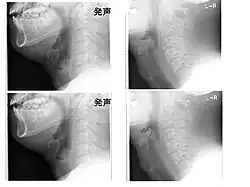

CT imaging showing the "halloween sign"

Left column: Normal epiglottis. Right column: Epiglottitis.

On lateral C-spine X-ray, the thumbprint sign describes a swollen, enlarged epiglottis.[11] A normal X-ray, however does not exclude the diagnosis.[11] An ultrasound may be helpful if specific changes are present, but its use as of 2018 is in the early stages of study.[11]